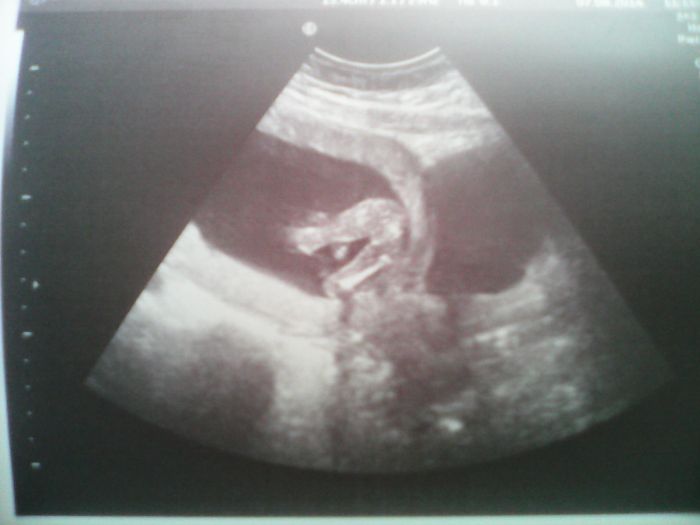

Ahoj holky....mám po kontrole v poradně. Sestra mi sdělila,že mi tt budou počítat už podle ultrazvuku,takže místo 15+5tt,jsem už 16+3tt. Mimčo bylo akční,měří 11cm,váží 110gr. Pohlaví mi lékař nepotvrdil,ale dal mi do příště kvízovou otázku,at hádám,co má mezi nožkama. Posílám foto mimča,jak na mě koukalo a pak tu,kde mám hádat pohlaví. Pokusíte se ho určit i vy? Další poradnu mám 4.9a další velký ultrazvuk 9.9,kdy se snad dozvím,co čekáme. Jinak stěry mi dopadly na výbornou a taky odběr na boreliozu byl negativní,takže je vše v naprostém pořádku.